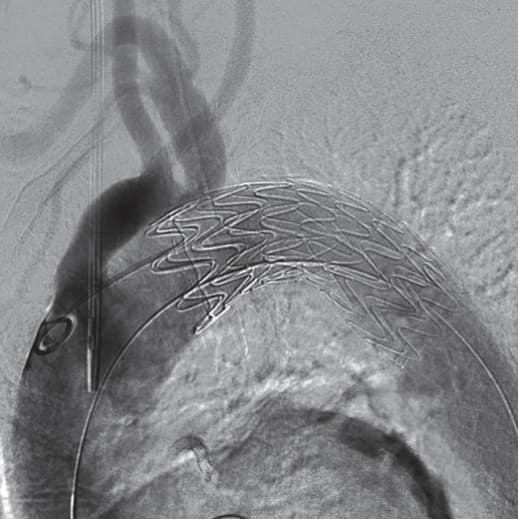

右総大腿動脈に6 Frシースを留置し、アクセスとした 。ラジフォーカスTMガイドワイヤーM**および 5 Frピッグテールカテーテルを上行大動脈まで進行させ、manipulateしたEgoist® EGU35-AC300Q (Arch Curve)ガイドワイヤーを大動脈基部まで到達させた。この時点で透視下にガイドワイヤー押し付けを行い、安定した状態で大弯側に押し付け可能なこと、左室内へ迷入しないことを確認した。22 Frゴア®ドライシール フレックス イントロデューサシースを進行させ、引き続きTAG® コンフォーマブル ステントグラフトTGMR373710Jを適正位置まで進行させた。DSAを施行し、左総頚動脈(LCCA)および左鎖骨下動脈(LSCA)の位置を確認した。ここからは、術者(ドライシールシース固定およびデリバリーカテーテルの操作)・助手(デリバリーカテーテルの固定、ガイドワイヤーの押し付け)の共同操作にて一次・完全展開を行った。ガイドワイヤーを軽く押し付けた状態で、パーシャルアンカバーステントがLCCAに若干かかる位置で一次展開を施行した。ガイドワイヤーの押し付けを加えて、LCCA直下にパーシャルアンカバーステントが位置するように微調整を行った。DSA上のZone 2レベルの小弯側に合わせて、アンギュレーションコントロールダイヤルを回転させて至適な角度に調整した。ガイドワイヤーを押し付けた状態で完全展開を施行した。DSAを施行し、コアキシャルに留置されていること、特に小弯側が至適角度で留置されていることを確認し、この時点でのアンギュレーションコントロールは必要ないと判断した。ガイドワイヤーを用いて、慎重にピッグテールカテーテルを抜去し、引き続き完全展開を施行した。DSAを施行し、エンドリークが無いことを確認した。左上腕動脈よりアクセスし、LSCA根部で造影した。DSA上、明らかなType ll エンドリークを認めず、deployment sleeve部分を含むステントグラフトにてLSCA根部が完全に被覆・閉鎖されていることが確認できた。

結果・術後経過

エンドリークを認めず、初期治療が成功した。術後脳神経学的合併症を認めなかった。術後確認CTにおいてもエンドリークを認めず、軽快退院した。